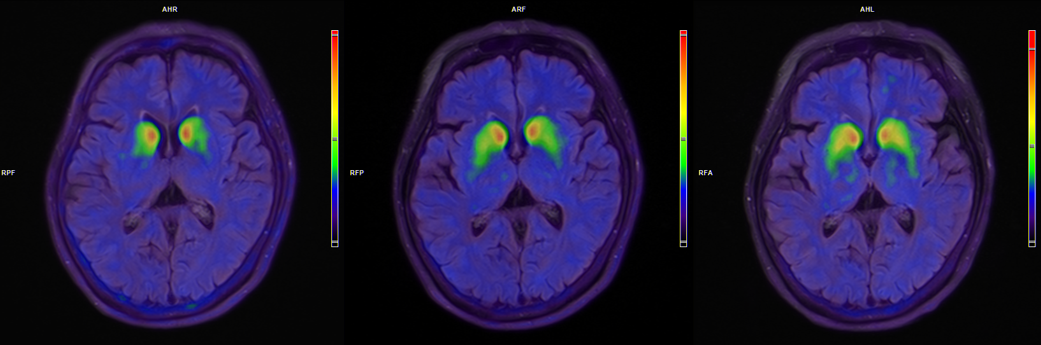

该患者整体耐受良好,无严重不良事件及与移植细胞相关的不良事件。《MDS统一帕金森病评定量表(MDS-UPDRS)》评分第Ⅲ部分在“关”期改善21分,在“开”期改善9分,改善幅度均超过45%。每日“关”期平均减少3.6小时,不伴有恼人运动障碍每日“开”期增加3.3小时。《帕金森病非运动症状评价量表(NMSS)》量表及《帕金森病患者生活质量量表(PDQ-39)》均出现改善,18F-FP-CIT PET影像学显示,双侧壳核移植区多巴胺转运体信号持续增强。

患者脑部术前、3个月、6个月的18F-FP-CIT PET图像